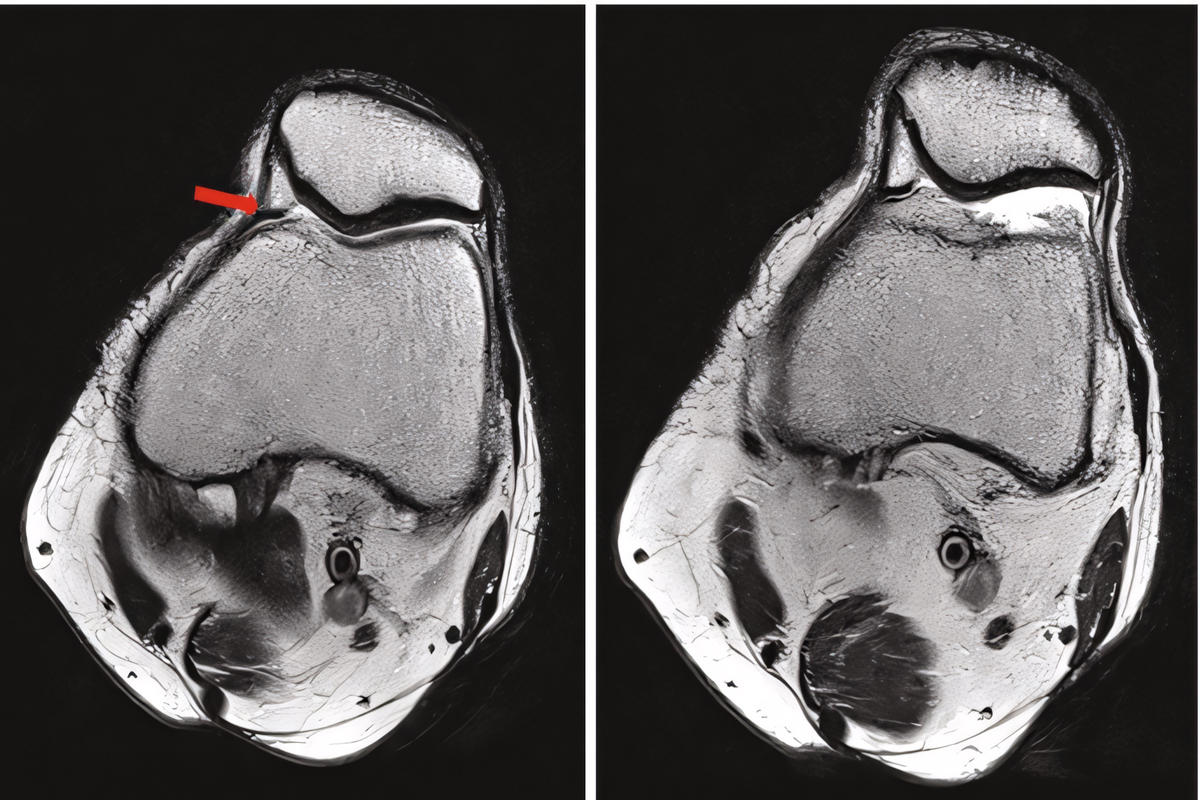

• Μαγνητική τομογραφία (MRI) για αποκλεισμό άλλων ενδαρθρικών παθήσεων

Η MRI δεν είναι πάντα διαγνωστική για το plica syndrome, αλλά βοηθά στον αποκλεισμό άλλων αιτιών πόνου στο γόνατο.